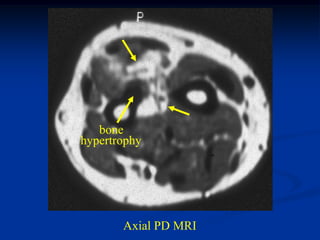

Case #1205

38 year female with

hemangioma forearm

with hypertrophic response

in subadjacent ulna

Bone scan

bone

hypertrophy

Axial PD MRI

Axial gad contrast MRI

Sagittal T-2 MRI